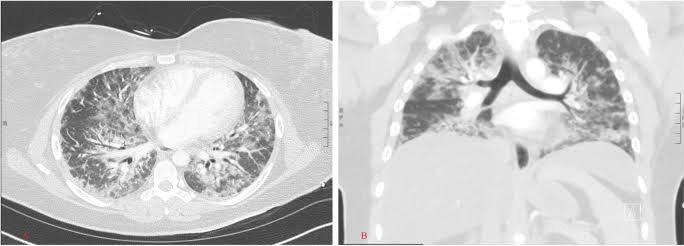

Ghosh recuerda que McGonagle le habló de pacientes con lesiones pulmonares graves, algunos de los cuales presentaban síntomas reumatológicos (erupciones cutáneas, artritis, dolor muscular) que, a menudo, acompañan la enfermedad pulmonar intersticial. McGonagle tenía curiosidad por saber si existía una conexión entre la dermatomiositis positiva para MDA5 y el covid-19.

Un total de 25 pacientes desarrollaron cicatrices pulmonares (enfermedad pulmonar intersticial) y 8 personas del grupo mostraron un cuadro lo suficientemente grave como para provocar la muerte debido a la fibrosis progresiva. Ghosh señaló que existían perfiles clínicos establecidos de enfermedades autoinmunes MDA5. "Pero esto fue diferente", advirtió. "Fue diferente en el comportamiento y la tasa de progresión, y en el número de muertes", expuso.